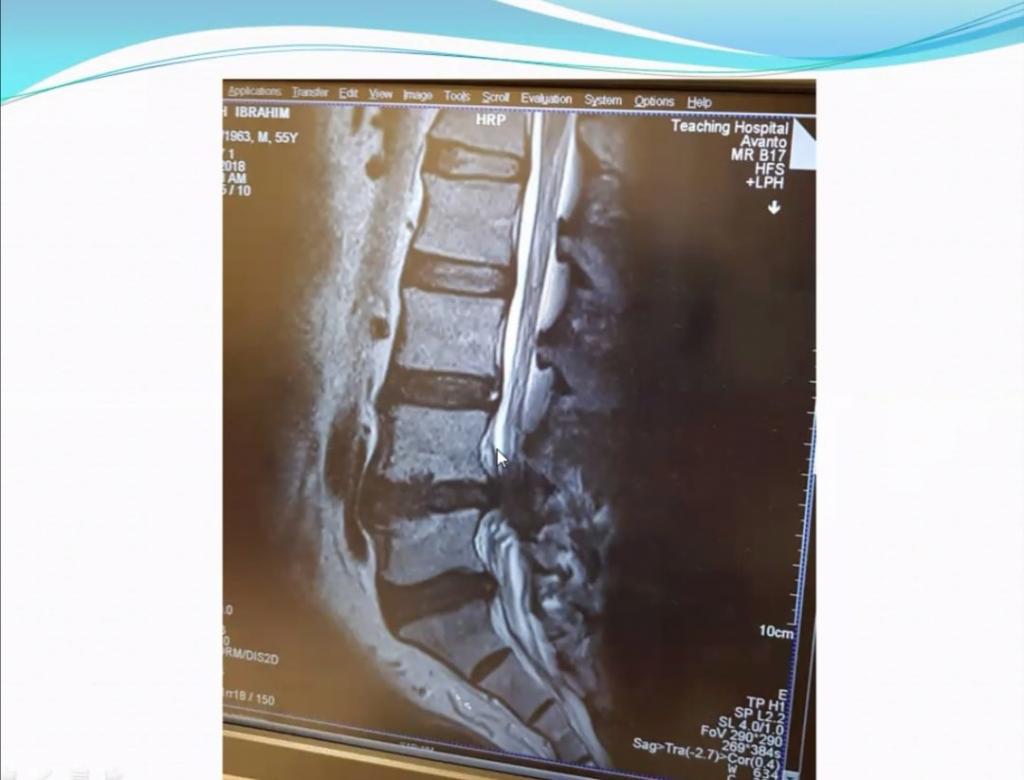

ألقى خلالها الاستاذ المساعد الدكتور ابي رامز البكري من كلية التربية البدنية وعلوم الرياضة محاضرة تناولت مواضيع عن التأثيرات الوقتية و الدائمية لمهنة طب الاسنان على قوام الجسم العضلي و العظمي لطبيب الاسنان نتيجة الحركات الخاطئة التي يتبعها خلال عمله ومزاولته للمهنة.